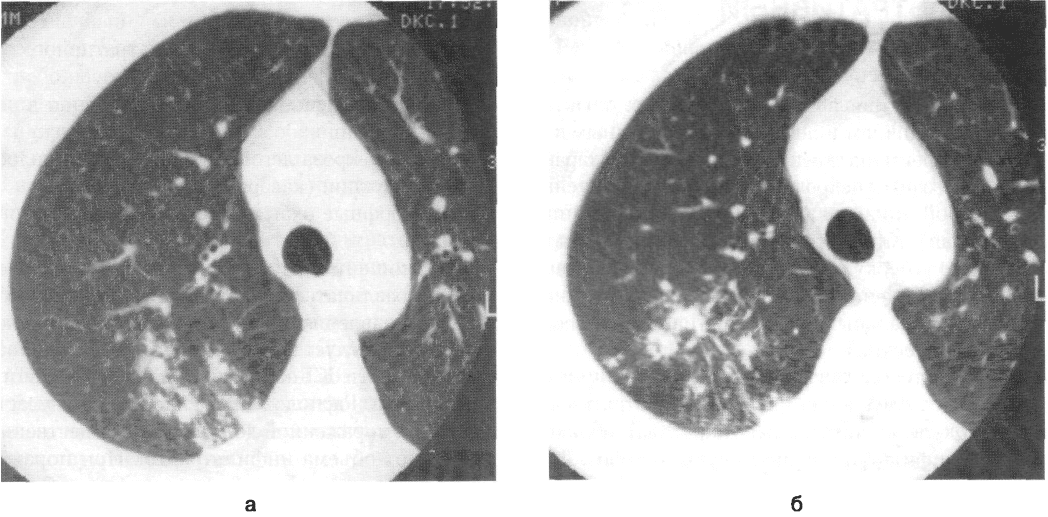

Иллюстрации по теме очагового и инфильтративного туберкулеза